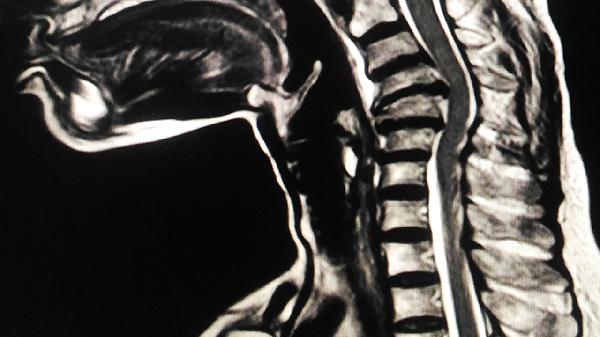

脊髓病的治疗主要包括药物治疗、物理治疗、手术治疗等方式。脊髓病可能与感染、外伤、血管病变、退行性病变、肿瘤等因素有关,通常表现为肢体无力、感觉障碍、大小便功能障碍等症状。建议及时就医,在医生指导下选择合适的治疗方案。

对于肿瘤压迫、椎间盘突出等引起的脊髓病,可能需要行椎管减压术、肿瘤切除术等手术治疗。急性脊髓损伤患者可能需要紧急手术解除压迫。手术方式需根据具体病情选择,如椎板切除术、椎间盘切除术等。术后需配合康复治疗促进功能恢复。